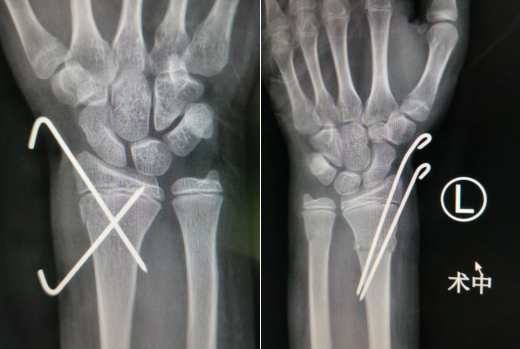

在助手牵拉对抗作用下,刘医生在唐医生团队共同努力下将患者骨折的部位分别予以牵引复位,同时分别用两根克氏针固定住骨折端,手术一切顺利。在病房休养了一天后,橙橙便出院回家了。